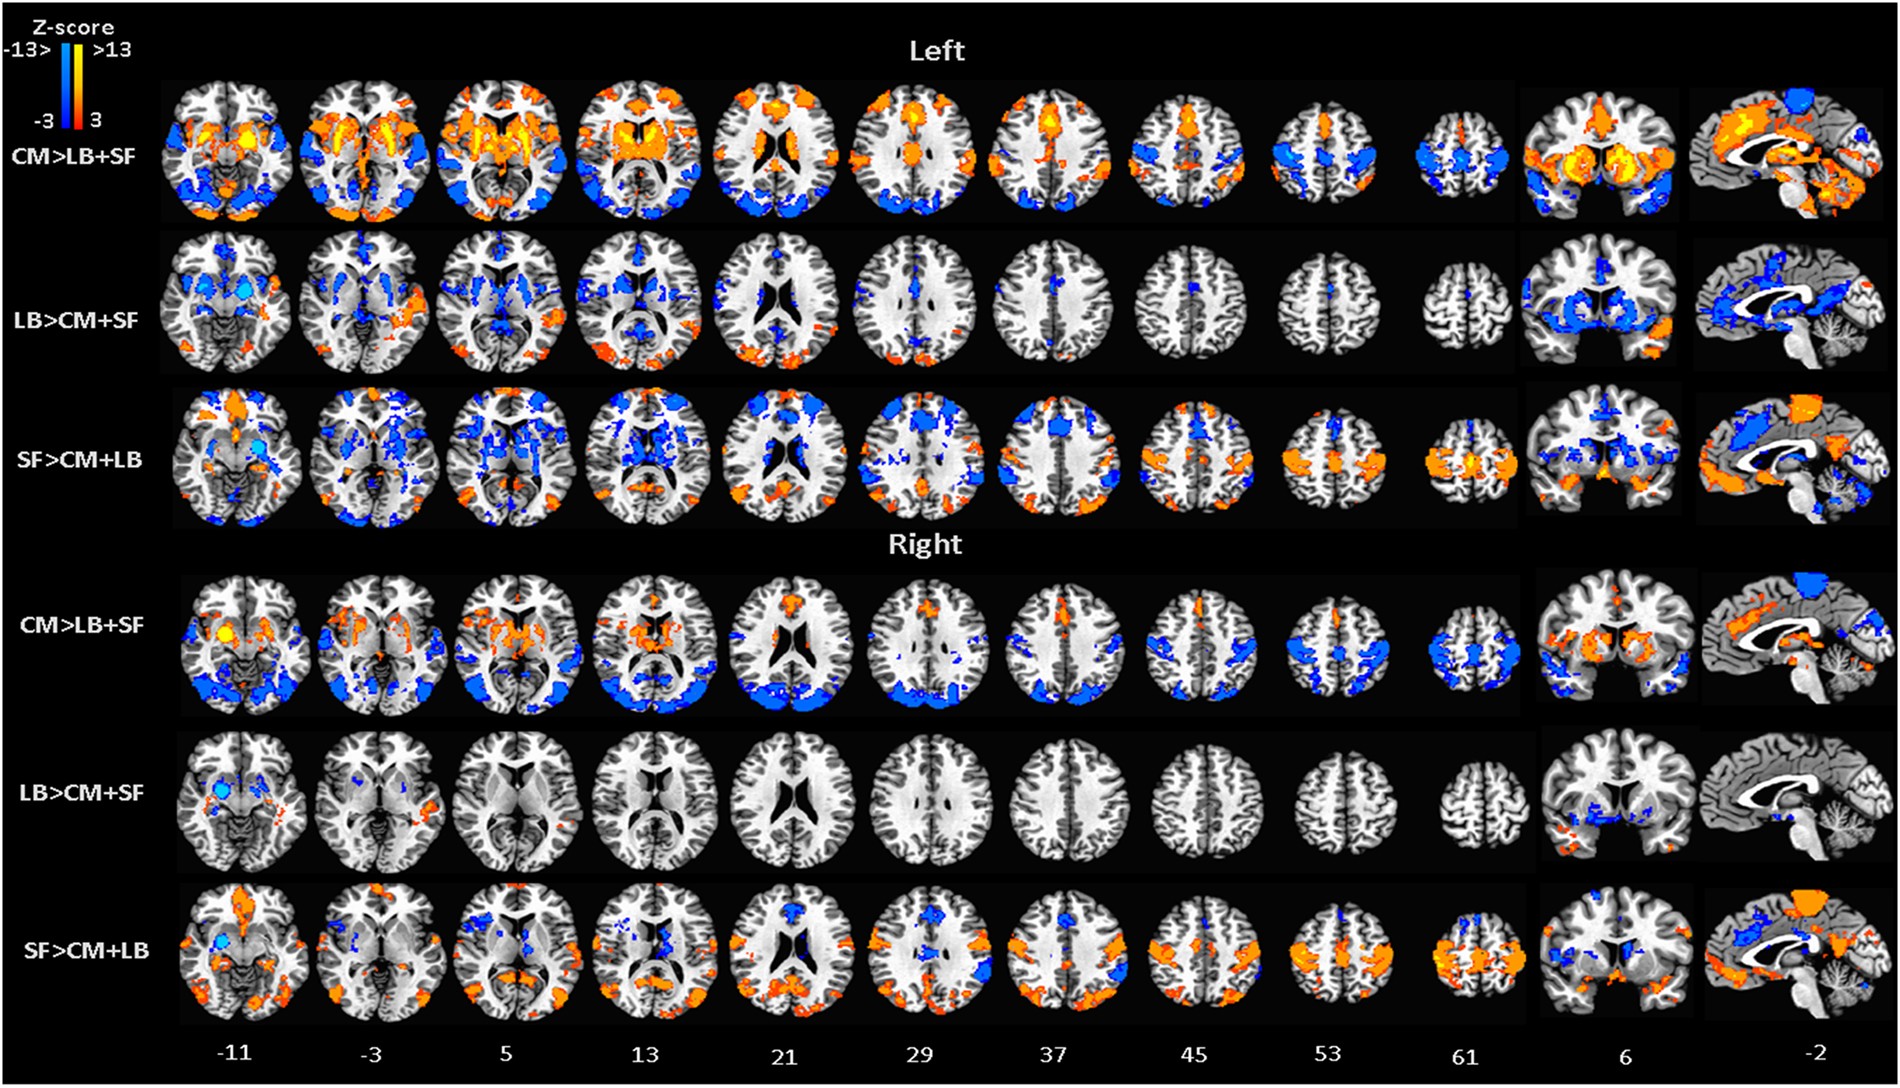

Figure 3

From: Graph theory reveals amygdala modules consistent with its anatomical subdivisions

FC-differential maps contrasting the connectivity map of each amygdala subdivision, CM, LB and SF, against the average connectivity pattern of the other two subdivisions, LB + SF, CM + SF, CM + LB. MNI standard space; radiological convention; significance: p < 0.05 FWE corrected.